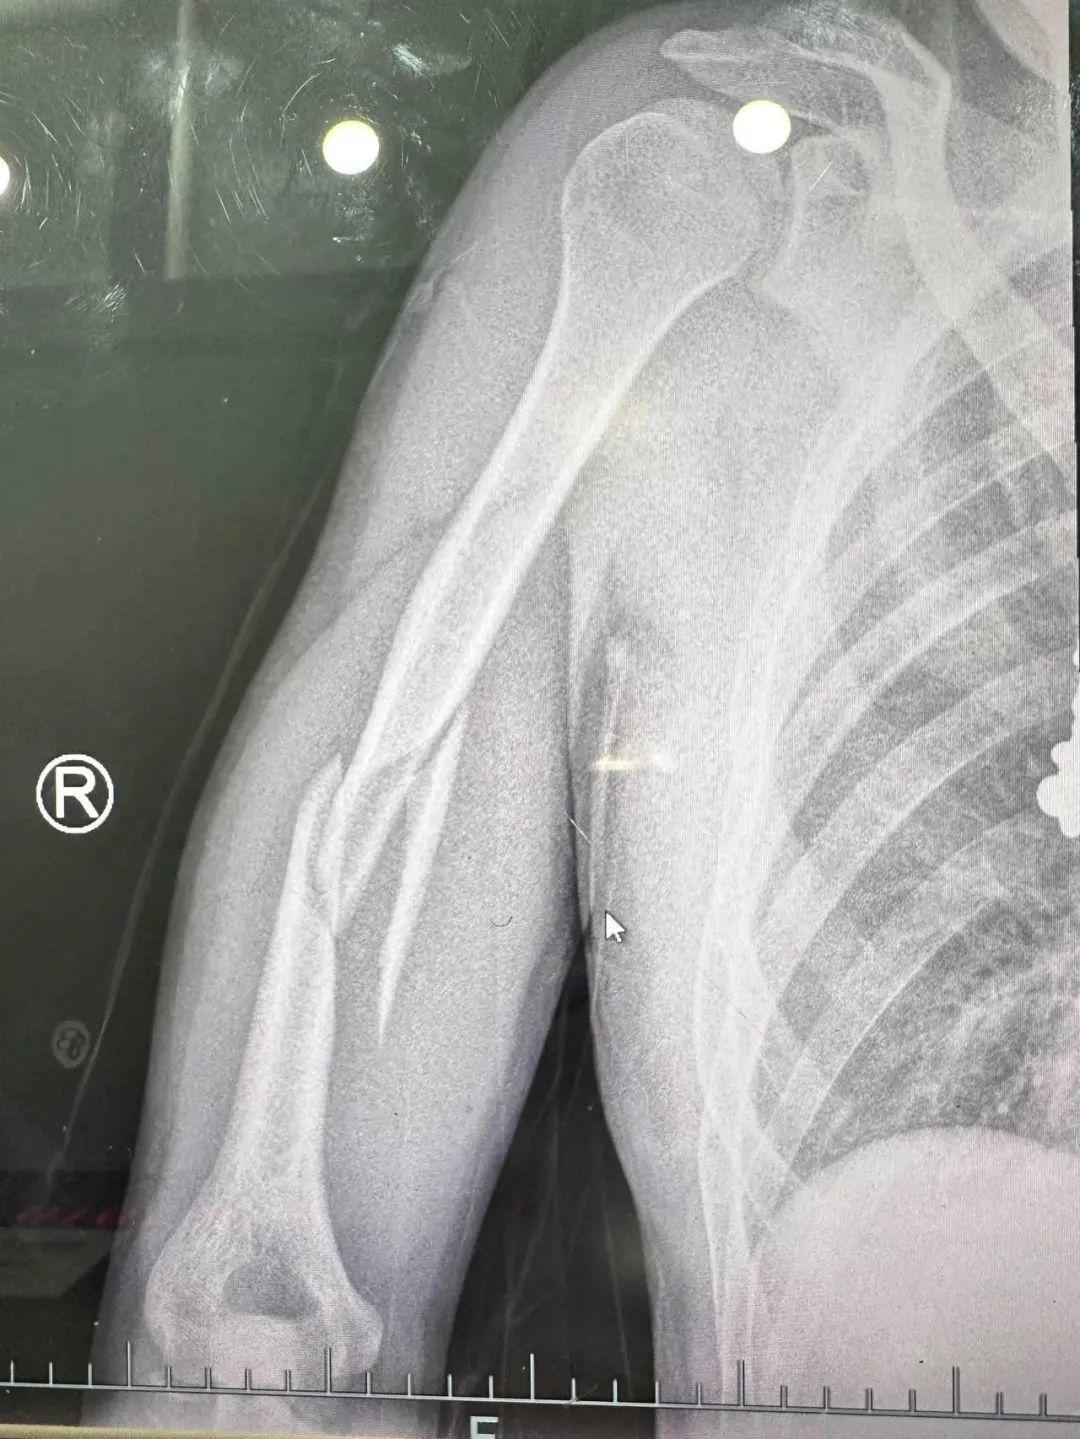

接诊的急诊科医生邵尉在详细询问病情后,迅速为小胡安排了X光射线检查。影像显示,小胡发生了“肱骨干断裂”而且周围软组织明显肿胀,情况十分严重。

由于小胡螺旋形骨折移位太严重,没办法保守治疗,最后不得不采用了手术用钢板内固定,在右臂上留下了一道20多公分的伤疤,需要很长时间康复。

无独有偶,仅仅一周后的夜晚,一名33岁的年轻男子栾先生(化名),也因为掰手腕导致上臂疼痛难忍,被紧急送到急诊科。急诊科医生肖晨在经过详细检查后,发现他的右上臂骨头竟然断成了三截!之后,栾先生也不得不接受手术治疗。